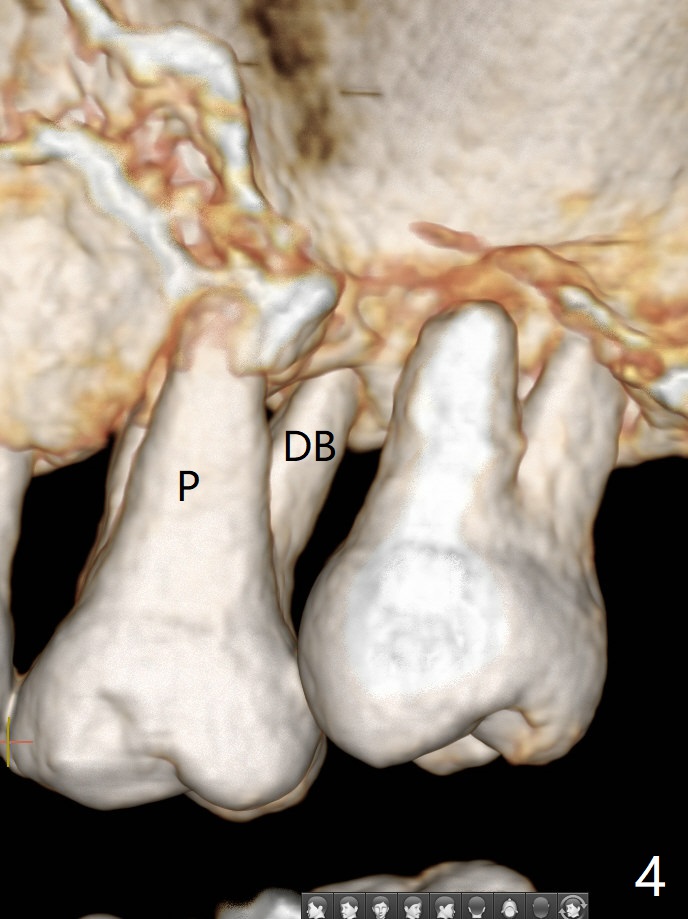

45岁女右上7严重骨质吸收终于开始出现症状(图一),虽然邻牙(6)骨质吸收也明显(图二,四,六,八,十),但是保留它,远中颊侧(DB),腭侧(P)根成为骨粉(图三,五,七,九,十一:红圆圈)支架。